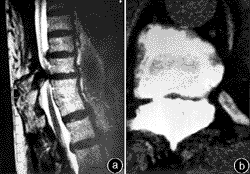

4.MRI檢查 主要用於觀察骨化的黃韌帶與脊髓的關係一般列為常規檢查尤其是擬行手術的病例(圖1)。